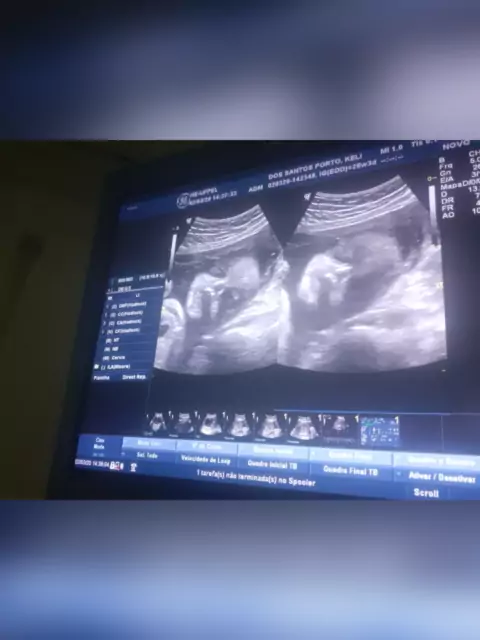

amor por esse ultrassom